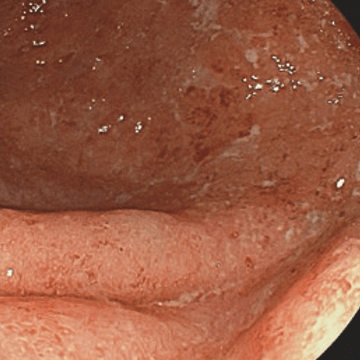

Минимальная активность воспалительного процесса:

yazvennyi_kolit.png

ЯК миним акт-min.png

Минимальная активность

Гиперемия и отек

диффузные

Зернистость

нет

Сосудистый рисунок

смазанный

Кровоточивость

субэпителиальные геморрагии

Эрозии

единичные

Язвы

отсутствуют